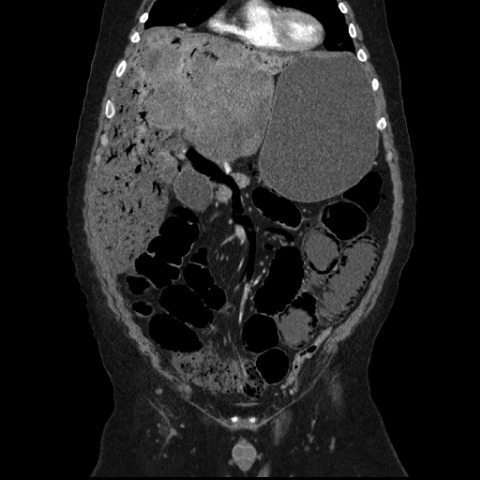

With regard to in-hospital complications, there were nine intensive care unit transfers (one for myocardial infarction, one for stress-induced transient apical ballooning syndrome [Takotsubo cardiomyopathy [16]], and seven for hypertensive crises requiring i.v. vasodilators) and three groin hematomas. There was one in-hospital death associated with air in the portal venous system, a very rare complication after HAE [17] (Fig. 2). One of 174 hospitalizations was associated with death within 1 month postprocedurally, for a 30-day mortality rate of 0.5% per HAE-related hospital stay and one death in 72 patients (1.4%).

Figure 2.

Coronal computed tomography scan of the abdomen/pelvis showing air in the portal venous system and pneumatosis intestinalis following hepatic artery embolization.

The low 30-day mortality rate among our patients is comparable with, or slightly better than, the rates reported in other postembolization outcome studies [5, 25]. It is also comparable with the 1% mortality rate seen in an analysis of HAI for the treatment of colorectal liver metastases in a study with a much larger sample size of 4,580 cases [26]. The fatal complication of portal venous gas has been previously observed after HAE [17], and its physiologic cause remains speculative at best, possibly resulting from the diffusion of gas from surrounding necrotic embolized tissue. In this case, the patient's postembolization course was marked by persistent nausea and abdominal pain that were refractory to standard interventions, and he would not have been dismissed from the hospital even if less stringent discharge criteria had been in place at that time.